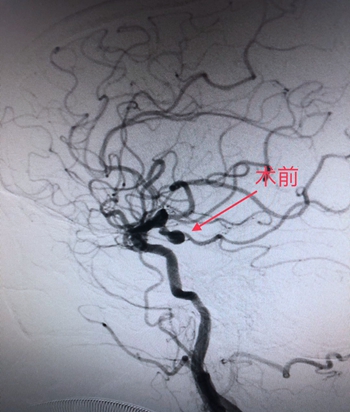

“沙场老将”力挽狂澜

从入院到入手术室,用时不到30分钟。经得患者家属同意,在麻醉科医生精准麻醉和严密检测下,手术由神经外科主任、神经介入科主任廖驭国作主刀,在神经外科李海堃副主任医师的配合下为患者进行颅内动脉瘤栓塞术,术中造影见患者血管迂曲成角,使导丝的通过造成困难和挑战,手术难度极高。廖主任凭借“久经沙场”的经验,以“绣花”功夫,最终完美栓塞破裂动脉瘤,顺利完成手术。

(术前DSA图)                                                        (术后DSA图)